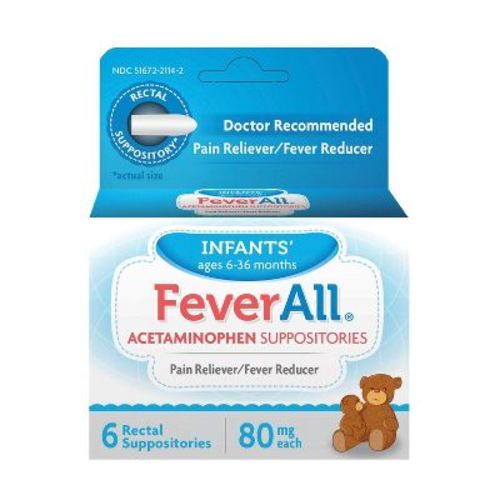

Wants: 2

Taro Rx FeverAll Infant Pain Reliever & Fever Reducer Suppository - Acetaminophen - 6ct

walmart Icon

target Icon

amazon Icon

$6.53

I purchased this